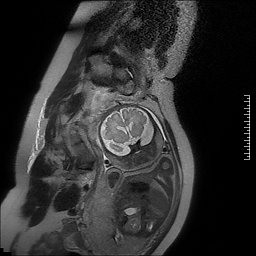

1.胎儿MRI扫描:胎儿成像的首选检查手段为超声,其操作简单,无创,快速,实时,价格低廉,特别适合大范围人群筛查,但也有不足之处,如超声难以穿越胎儿颅骨,视野偏小,对母体肥胖,有子宫肌瘤,羊水过少,多胎等情况时,对胎儿显示效果欠佳。磁共振则不受到这些因素影响,对羊水过少,双胎,及孕晚期胎头入盆或胎儿颅骨骨化,胎儿磁共振可以起到明显的补充作用。